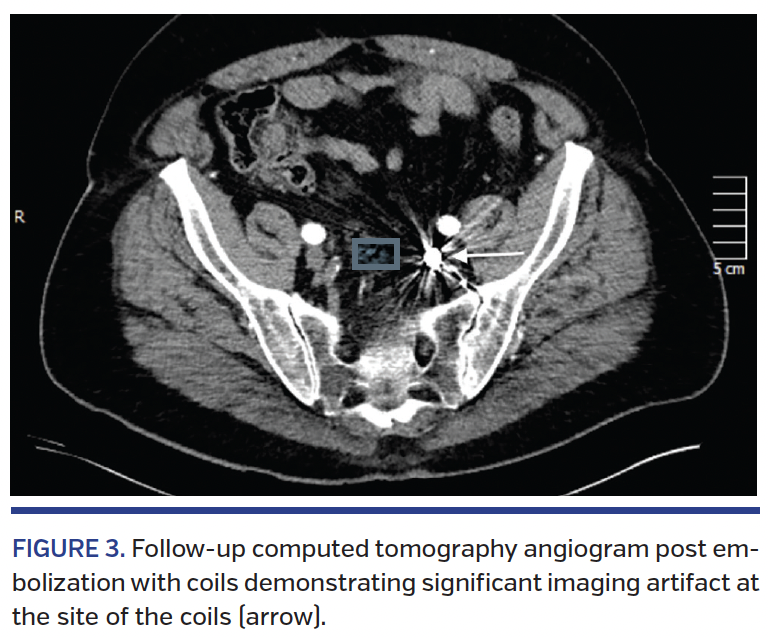

Postembolization CTAs of the 3 cases that returned for follow-up (60%) demonstrated clinically significant occlusion with no contrast filling of the aneurysm (grade D). However, there were significant CT imaging artifacts in all 3 cases (100%) graded as severe (grade 3) (Figure 3). No further CTA imaging was obtained in these patients following complete occlusion. Two of the patients from cohort #1 died from non-cardiac causes prior to follow-up CTA.